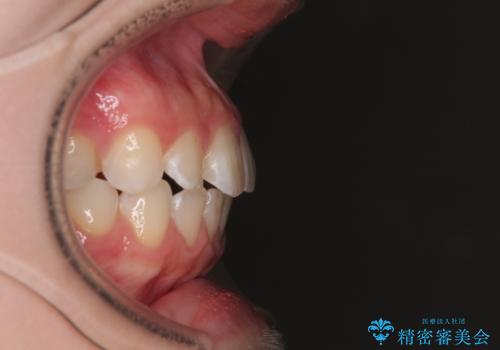

- 上下前歯部のデコボコを気にして来院された患者様です。

叢生は軽度であったため、マウスピースでもワイヤー装置でも対応可能でしたが、マウスピースを長時間使用する自信がないとのことでワイヤー装置にて矯正治療を行うこととしました。

叢生が軽度であったため、僅か半年で装置を除去することができました。